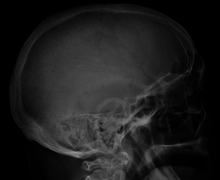

Bone pain affects almost 70% of patients and is the most common symptom.[11] Myeloma bone pain usually involves the spine and ribs, and worsens with activity. Persistent localized pain may indicate a pathological bone fracture. Involvement of the vertebrae may lead to spinal cord compression or kyphosis. Myeloma bone disease is due to the overexpression of receptor activator for nuclear factor κ B ligand (RANKL) by bone marrow stroma. RANKL activates osteoclasts, which resorb bone. The resultant bone lesions are lytic (cause breakdown) in nature and are best seen in plain radiographs, which may show "punched-out" resorptive lesions (including the "raindrop" appearance of the skull on radiography). The breakdown of bone also leads to release of calcium into the blood, leading to hypercalcemia and its associated symptoms.

The work-up of suspected multiple myeloma includes a skeletal survey. This is a series of X-rays of the skull, axial skeleton and proximal long bones. Myeloma activity sometimes appear as "lytic lesions" (with local disappearance of normal bone due to resorption), and on the skull X-ray as "punched-out lesions" (pepper pot skull). Magnetic resonance imaging (MRI) is more sensitive than simple X-ray in the detection of lytic lesions, and may supersede skeletal survey, especially when vertebral disease is suspected. Occasionally a CT scan is performed to measure the size of soft tissue plasmacytomas. Bone scans are typically not of any additional value in the workup of myeloma patients (no new bone formation; lytic lesions not well visualized on bone scan).